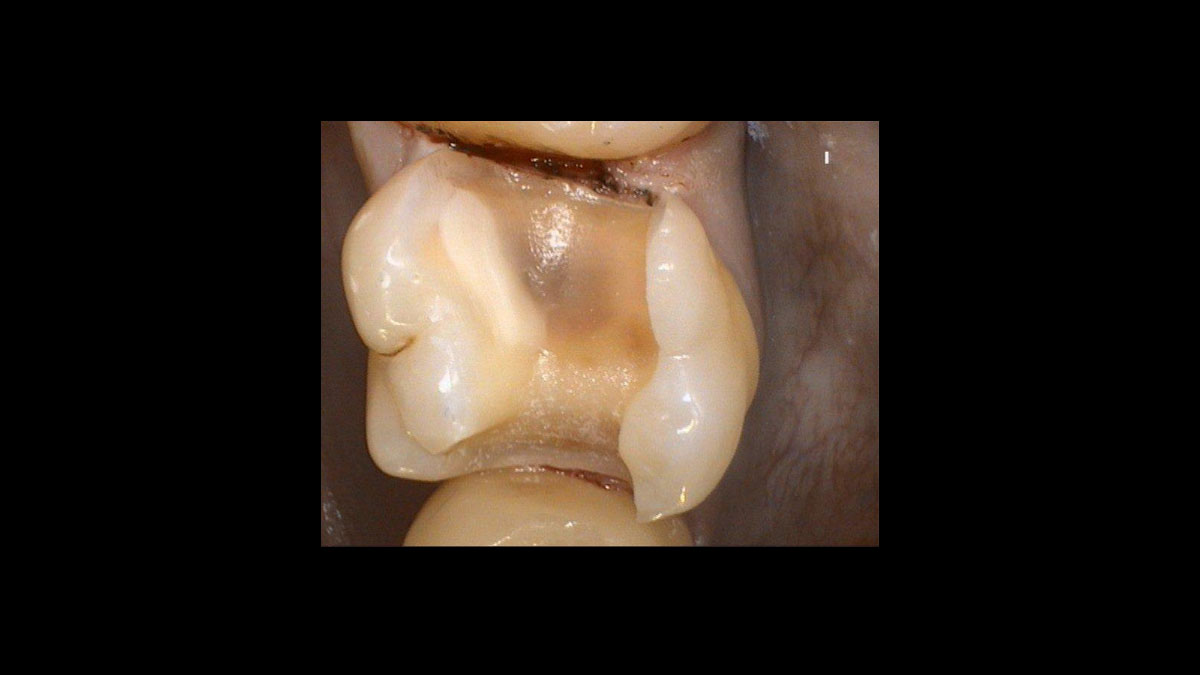

Gingival troughing